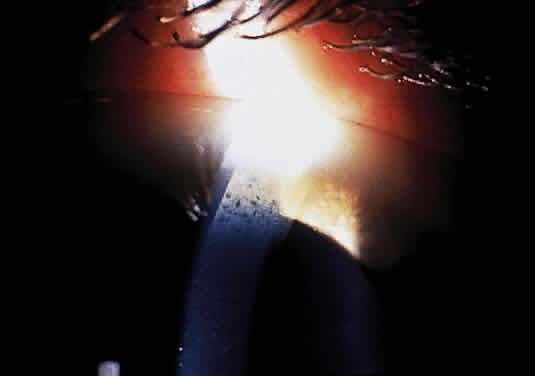

Corneal clouding (Fig. 10), hyperopic astigmatism, and a mild retinopathy with surface-wrinkling maculopathy (Fig. 11) appear to be the constant ocular triad.75 Some patients have retinal vascular tortuosity, optic nerve head swelling (Fig. 12), visual field defects, and abnormalities in color vision. Visual complaints are uncommon.

Fig. 10. Mild corneal clouding in a child with mucolipidosis III. (Traboulsi E, Maumenee I: Ophthalmologic findings in mucolipidosis III. Am J Ophthalmol 102:529, 1986)

Fig. 11. Surface-wrinkling maculopathy in a patient with mucolipidosis III. (Traboulsi E, Maumenee I: Ophthalmologic findings in mucolipidosis III. Am J Ophthalmol 102:529, 1986)

Fig. 12. Optic nerve head swelling in a patient with mucolipidosis III. (Traboulsi E, Maumenee I: Ophthalmologic findings in mucolipidosis III. Am J Ophthalmol 102:529, 1986)